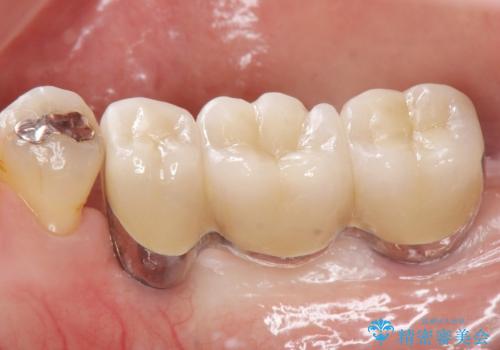

なるべく予算を抑えたいとのご希望から、上顎は入れ歯、右下臼歯部はインプラントによる治療を行いました。

上の前歯は動揺を抑え、入れ歯の着脱にも耐えうるように被せ物を連結させることにしました。

被せ物の種類:メタルボンドクラウン エコノミー

インプラントの種類:スプラインツイスト